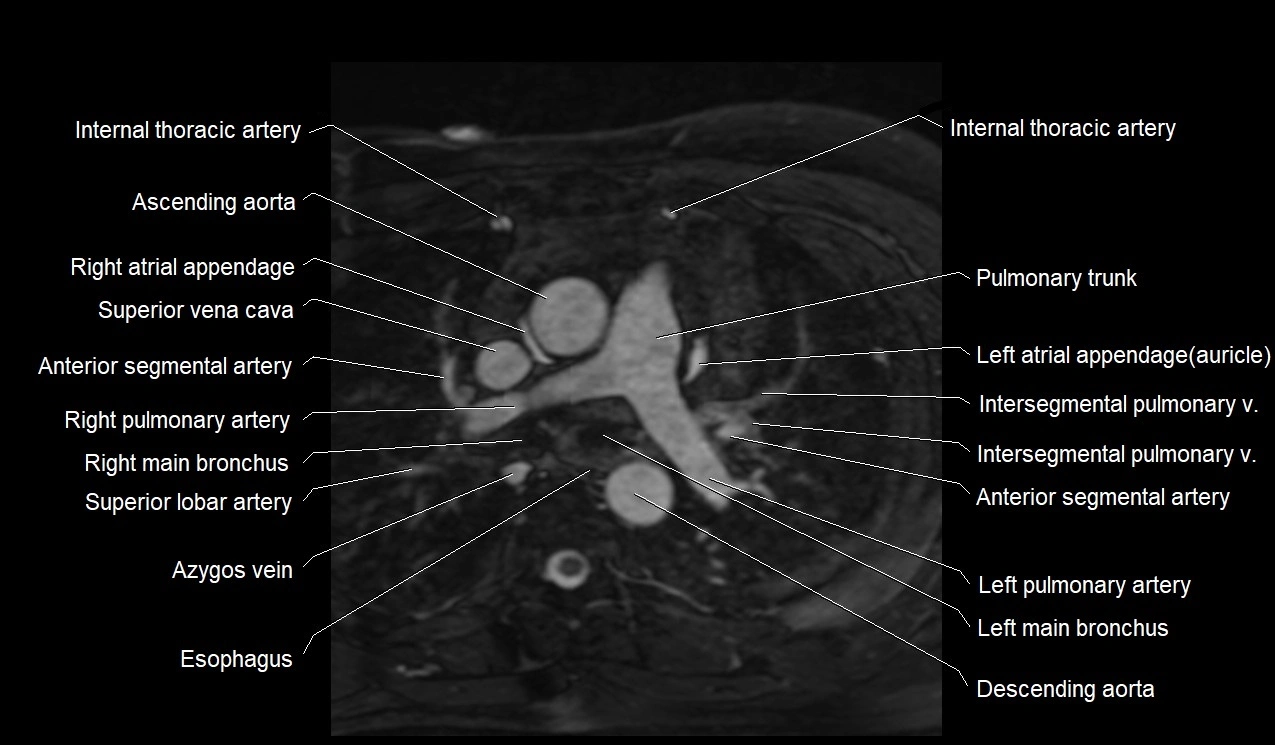

MRI image